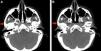

A head CT scan revealed a decrease in fat and subcutaneous tissue compared to the contralateral side (Fig. 2A and B).